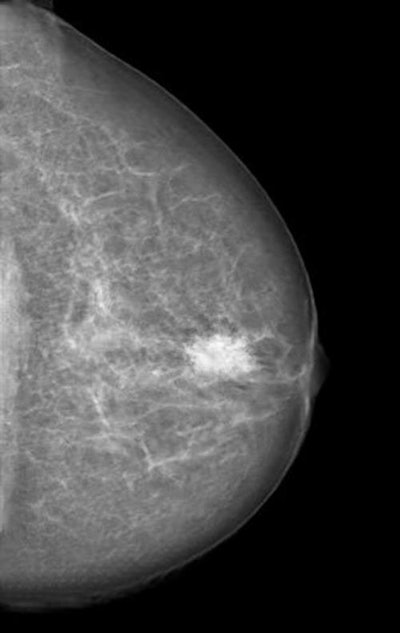

In a presentation on November 28, researchers from University Hospital Zurich and ETH Zurich in Switzerland will describe how they trained a cycle-consistent generative adversarial network (CycleGAN) to convert mammography images showing cancer into normal studies, as well as to convert normal control images into studies that show cancer. After three radiologists reviewed all of the images, none could reliably distinguish between the genuine and the modified cases.

"As doctors, it is our moral duty to first protect our patients from harm," said presenter Dr. Anton Becker in a statement. "For example, as radiologists we are used to protecting patients from unnecessary radiation. When neural networks or other algorithms inevitably find their way into our clinical routine, we will need to learn how to protect our patients from any unwanted side effects of those as well."

Attacks that could remove cancerous lesions from the image and replace them with normal-looking tissue won't be feasible for at least five years, Becker noted. However, he hopes to draw the attention of the medical community and hardware and software vendors, so they can address the issue while it's still a theoretical problem.